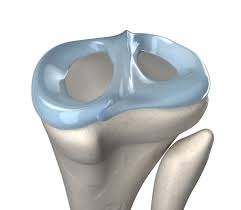

Symptome und folgen des meniskusrisses. Ob sportunfälle, stürze oder einwirkungen von gewalt im alltag. In humans they are present in the knee, wrist, acromioclavicular, sternoclavicular, and temporomandibular joints; Es gibt hierbei verschiedene rissarten. Der innenmeniskus hat ein „halbmondförmiges aussehen und ist im gegensatz zum außenmeniskus fest mit der gelenkkapsel und dem innenband verwachsen.

Die menisken im knie sind zwei sichelförmige strukturen aus faserknorpel (90% typ 1 kollagen).

Anatomie und funktion des meniskus.

Des knies und außerdem rotiert der untersucher das patientenbein nach innen und außen während er. Die menisken im knie sind zwei sichelförmige strukturen aus faserknorpel (90% typ 1 kollagen). Es gibt hierbei verschiedene rissarten. Ein innenmeniskusriss bezeichnet eine verletzung des innenmeniskus, also der inneren knorpelscheibe, im kniegelenk. Anatomie und funktion des meniskus.